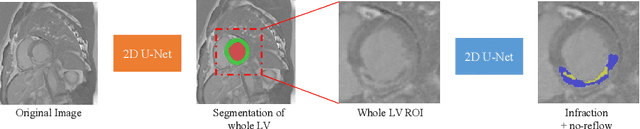

Automatic evaluation of myocardium and pathology plays an important role in the quantitative analysis of patients suffering from myocardial infarction. In this paper, we present a cascaded convolutional neural network framework for myocardial infarction segmentation and classification in delayed-enhancement cardiac MRI. Specifically, we first use a 2D U-Net to segment the whole heart, including the left ventricle and the myocardium. Then, we crop the whole heart as a region of interest (ROI). Finally, a new 2D U-Net is used to segment the infraction and no-reflow areas in the whole heart ROI. The segmentation method can be applied to the classification task where the segmentation results with the infraction or no-reflow areas are classified as pathological cases. Our method took second place in the MICCAI 2020 EMIDEC segmentation task with Dice scores of 86.28%, 62.24%, and 77.76% for myocardium, infraction, and no-reflow areas, respectively, and first place in the classification task with an accuracy of 92%.